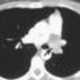

Pulmonary artery angiosarcoma